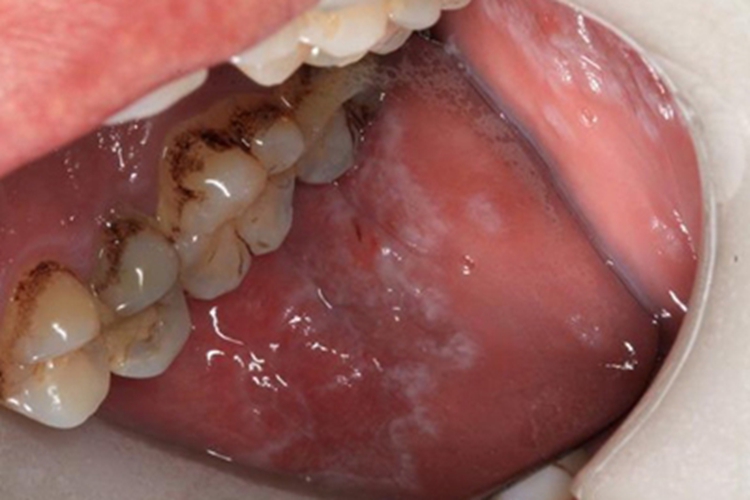

先天性角化不良患者口腔黏膜可发生异常,常因角化不良而表现为颊黏膜增厚,出现略高于黏膜表面的不规则散在白斑,广泛伴疣状增厚。